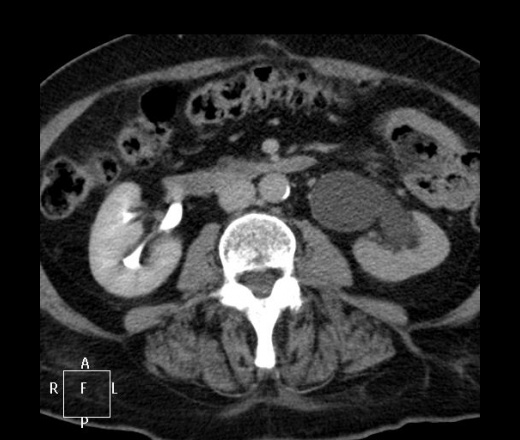

ID:54045

Приемный статус.

А, почему обязательно рецидив?

Перед операцией, аналогичное КТ делали?

Делали в октябре 2010 (не мной описана):